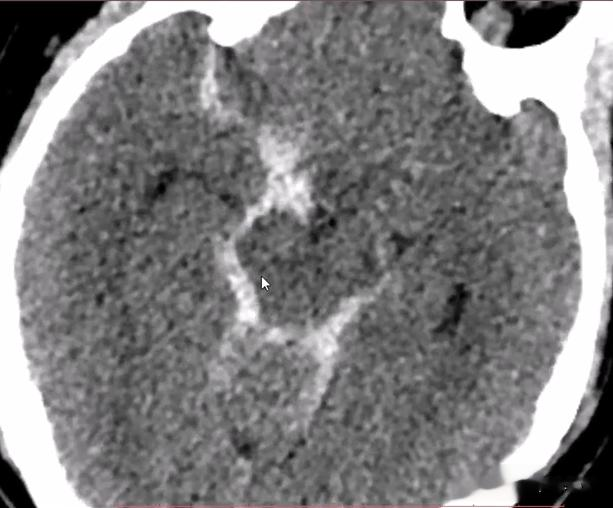

CT表现: 1.直接征象:为脑沟、脑池、脑裂密度增高 。 前动脉破裂 , 血液主要集聚于视交叉池、侧裂前部;大脑中动脉破裂 , 血液主要集聚于一侧侧裂 。

【动脉瘤|48岁女性,外伤后头痛剧烈,头颅CT发现了什么危急重症?】2.间接征象:脑积水、脑水肿、脑梗死、脑内血肿、脑室内积血、脑疝等 。 蛛网膜下腔出血位置常提示动脉瘤存在的部位 , 大脑外侧裂出血常提示大脑中动脉分叉处动脉瘤;大脑纵裂前部、视交叉周围出血提示前交通动脉瘤或前动脉瘤;脚间池、环池出血提示后交通动脉瘤或基底动脉瘤顶端动脉瘤;鼻咽或鼻腔出血提示虹吸部动脉瘤 。

蛛网膜下腔出血:环池及右侧外侧裂池高密度影填充